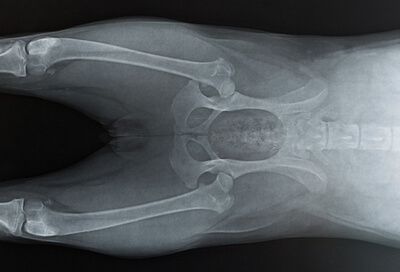

Best dog food for boxers 2025